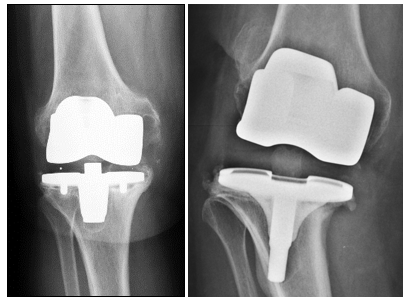

Ähnlich ist die Situation bei den in Tabletten- und Pulverform erhältlichen sogenannten „Chondroprotektiva“ (Glucosamin und Chondroitinsulfat). Ihnen wird ein schützender Effekt auf den Gelenkknorpel zugeschrieben, ein definitiver Beweis für die langfristige Wirksamkeit fehlt jedoch bisher. Bei zunehmenden Schmerzen und ungenügender Schmerzreduktion durch die nicht-operativen und gelenkerhaltenden Therapieverfahren kann die Entscheidung zum Kunstgelenk gegeben sein.